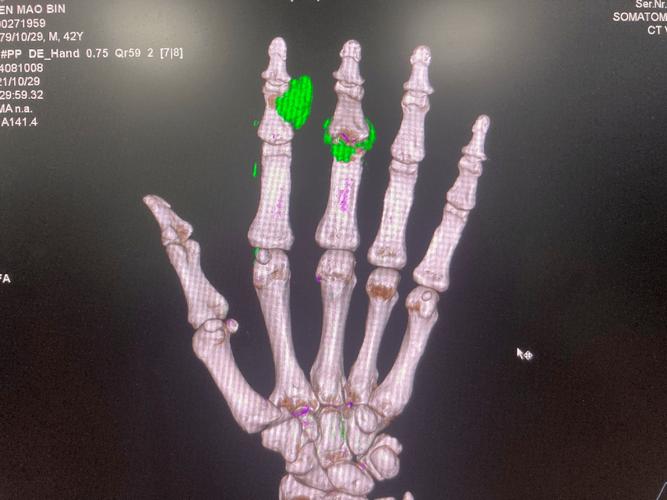

临床中,痛风的“金标准”仍是关节液或痛风石中尿酸盐结晶的显微镜检查,若发现针状或负性双折射的尿酸盐结晶即可确诊,而双源CT的价值在于,当患者无法进行关节液穿刺(如关节肿胀严重、有出血风险)或结晶检查阴性但高度怀疑痛风时,可作为重要的辅助诊断工具,研究显示,双源CT对痛风诊断的敏感性可达80%-90%,特异性接近100%,尤其在中晚期痛风患者中,能清晰显示痛风石的大小、形态及与周围组织的关系,帮助评估病情严重程度。

双源CT也存在局限性,其敏感性在早期或间歇期痛风中可能降低,此时尿酸盐结晶沉积较少,难以被CT检出;检查费用较高,且存在辐射暴露,不适用于常规筛查或孕妇;部分其他钙化性病变(如钙化性肌腱炎、血管钙化)可能被误判为尿酸盐结晶,需结合临床及实验室检查(如血尿酸水平)鉴别,双源CT结果需与患者症状(如急性关节炎发作史)、实验室检查(血尿酸、肾功能)及病史综合分析,不能单独作为确诊依据。

综上,双源CT是痛风诊断的重要辅助工具,可通过直接显示尿酸盐结晶为诊断提供有力支持,但“确诊”痛风仍需以关节液或痛风石结晶检查为核心,结合双源CT结果、临床症状及实验室数据进行综合评估,对于疑似痛风患者,建议在风湿免疫科医生指导下,个体化选择检查方案,以实现精准诊断和治疗。